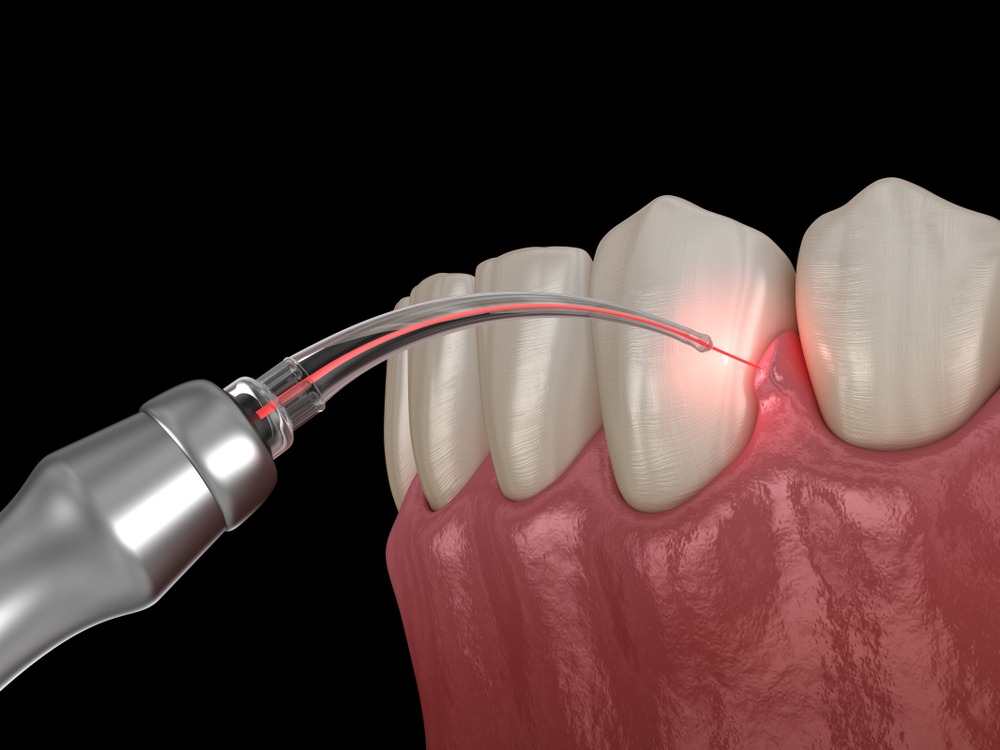

Advances in the medical and dental sciences have even allowed them to be used as treatment instruments. Yet even with our increased familiarity with laser technology, it’s still difficult for many to understand how it can be used by your general dentist to help treat gum and teeth problems.

Because of the accuracy to which laser beams can be tuned, they themselves are incredibly effective tools to fight gum disease. That’s because clinicians like Dr. Andres R. Sanchez are only allowed to treat the diseased areas, leaving the healthy tissue around untouched.

Not only does this destroy the decaying area, but it also helps to promote the growth of newer, healthier tissue in its place.